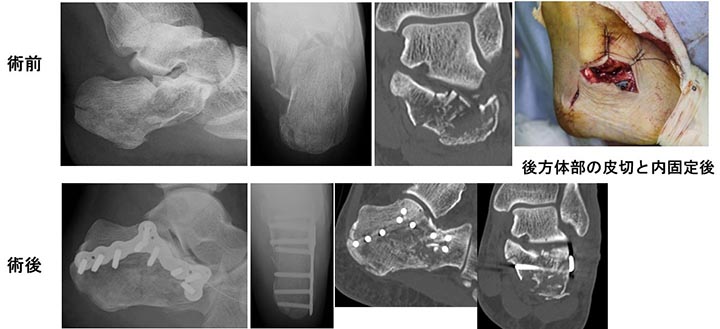

内固定方法は踵骨プレートを使用する方法とスクリューとピンのみを用いた小侵襲内固定法があります(図3)。近年、術後軟部組織の合併症の発生率を減少させるために、小切開にてプレート固定を行う、小侵襲プレート固定法も行われるようになっています(図4)。

図3. 踵骨骨折に対する手術療法

図4.MIPO法による踵骨関節内骨折の整復内固定